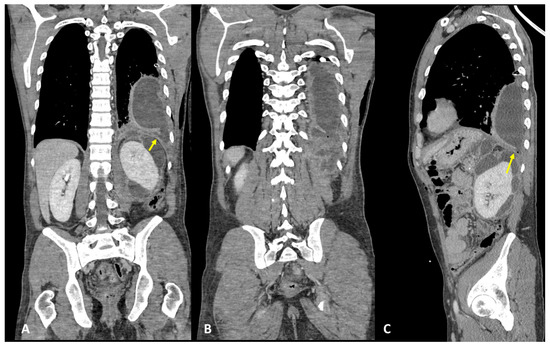

3.2. Case #2: Hepato-Thoracic Fistula